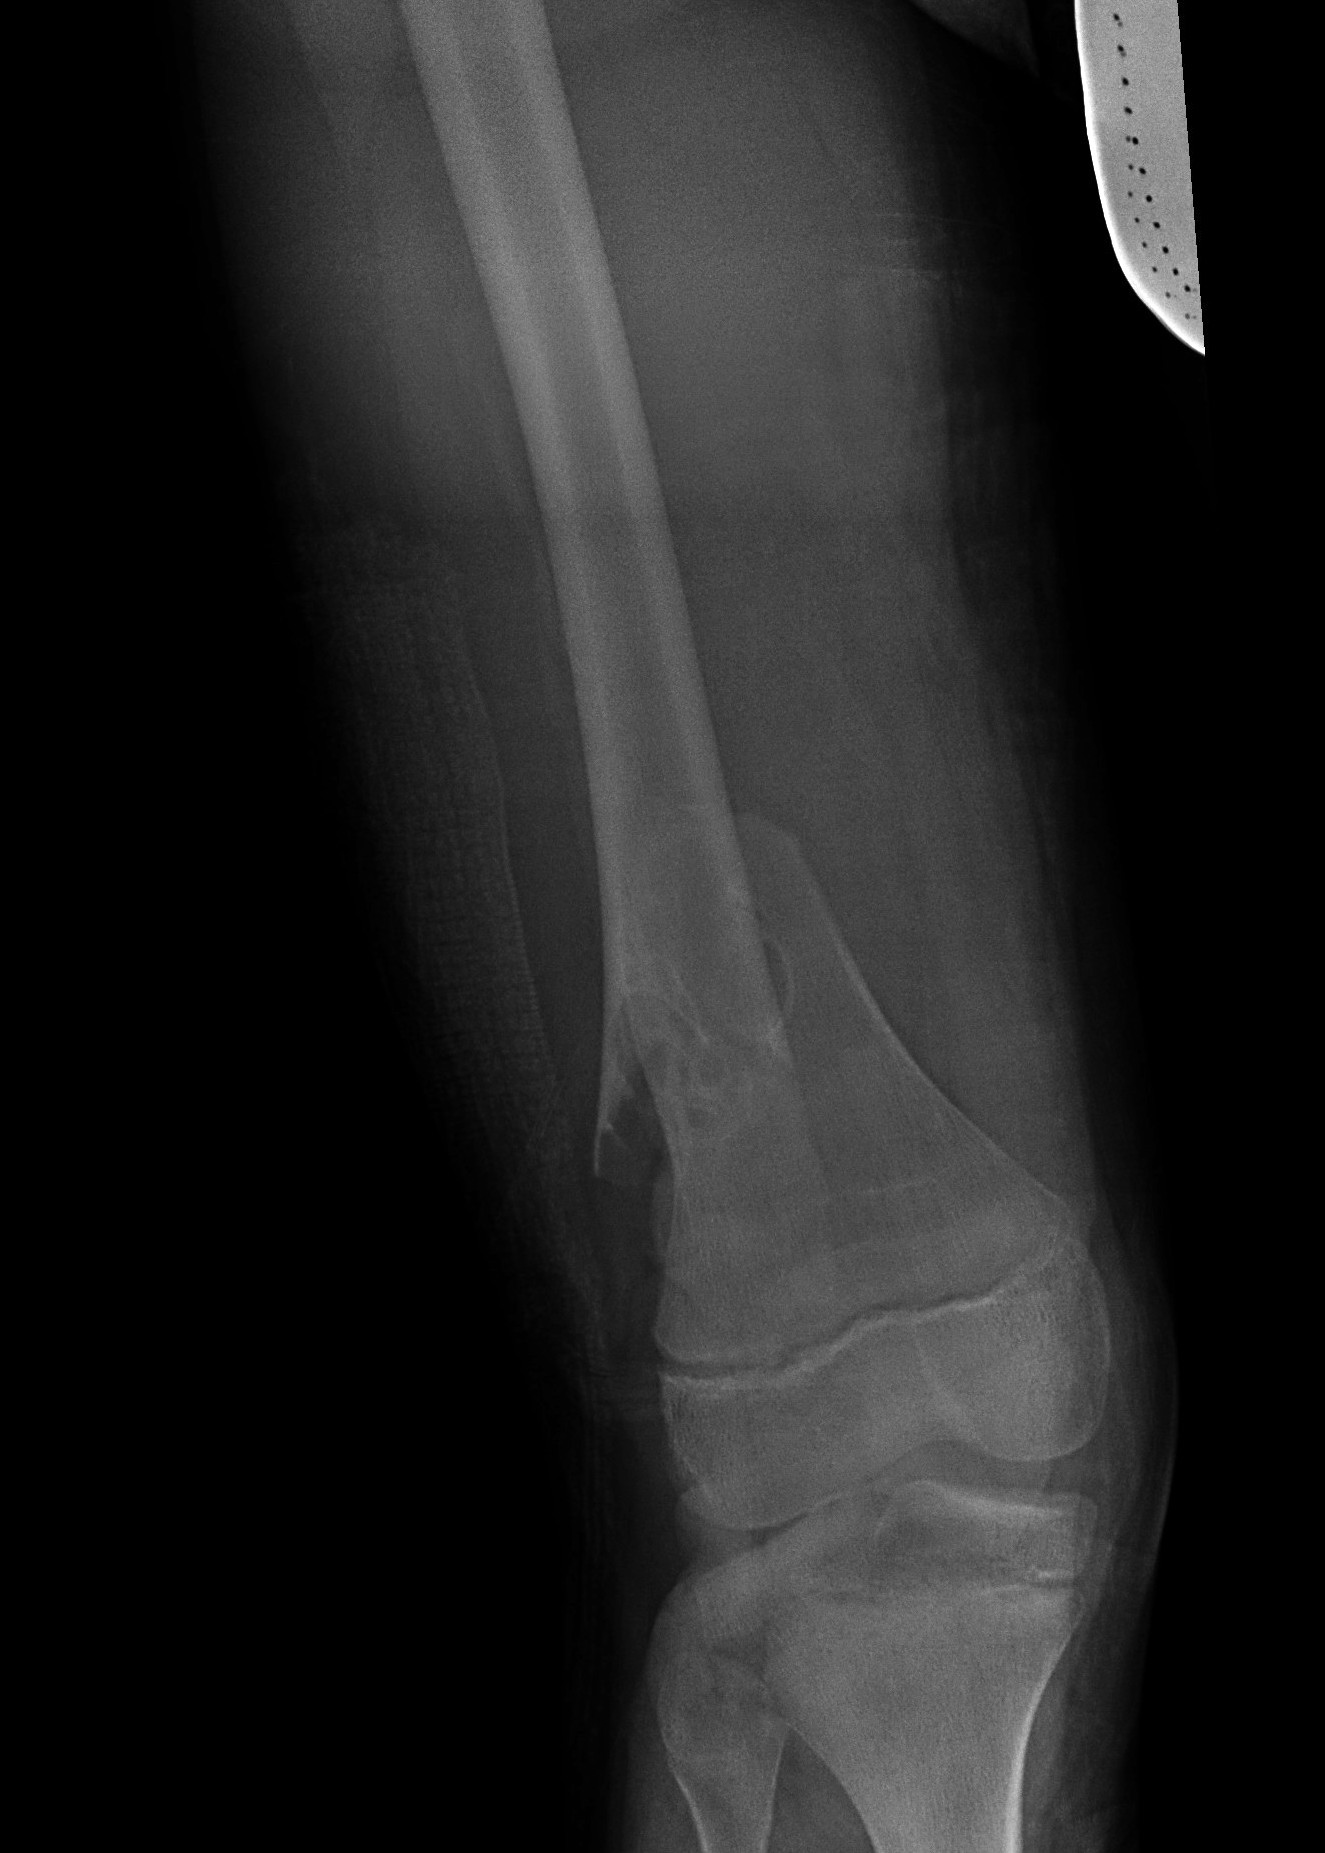

Distal Femoral Fracture SH2 APDistal Femoral Fracture SH2 Lateral

Salter Harris Type II